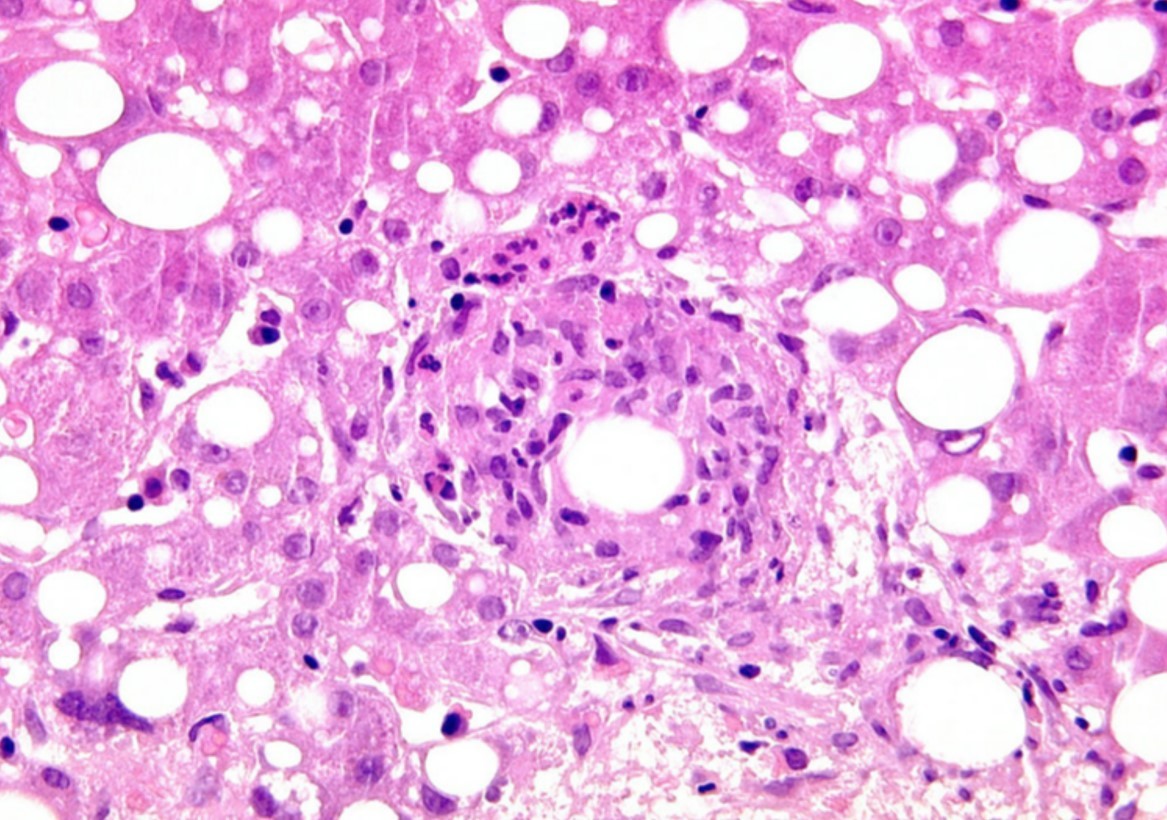

Postinfantile Giant Cell Hepatitis